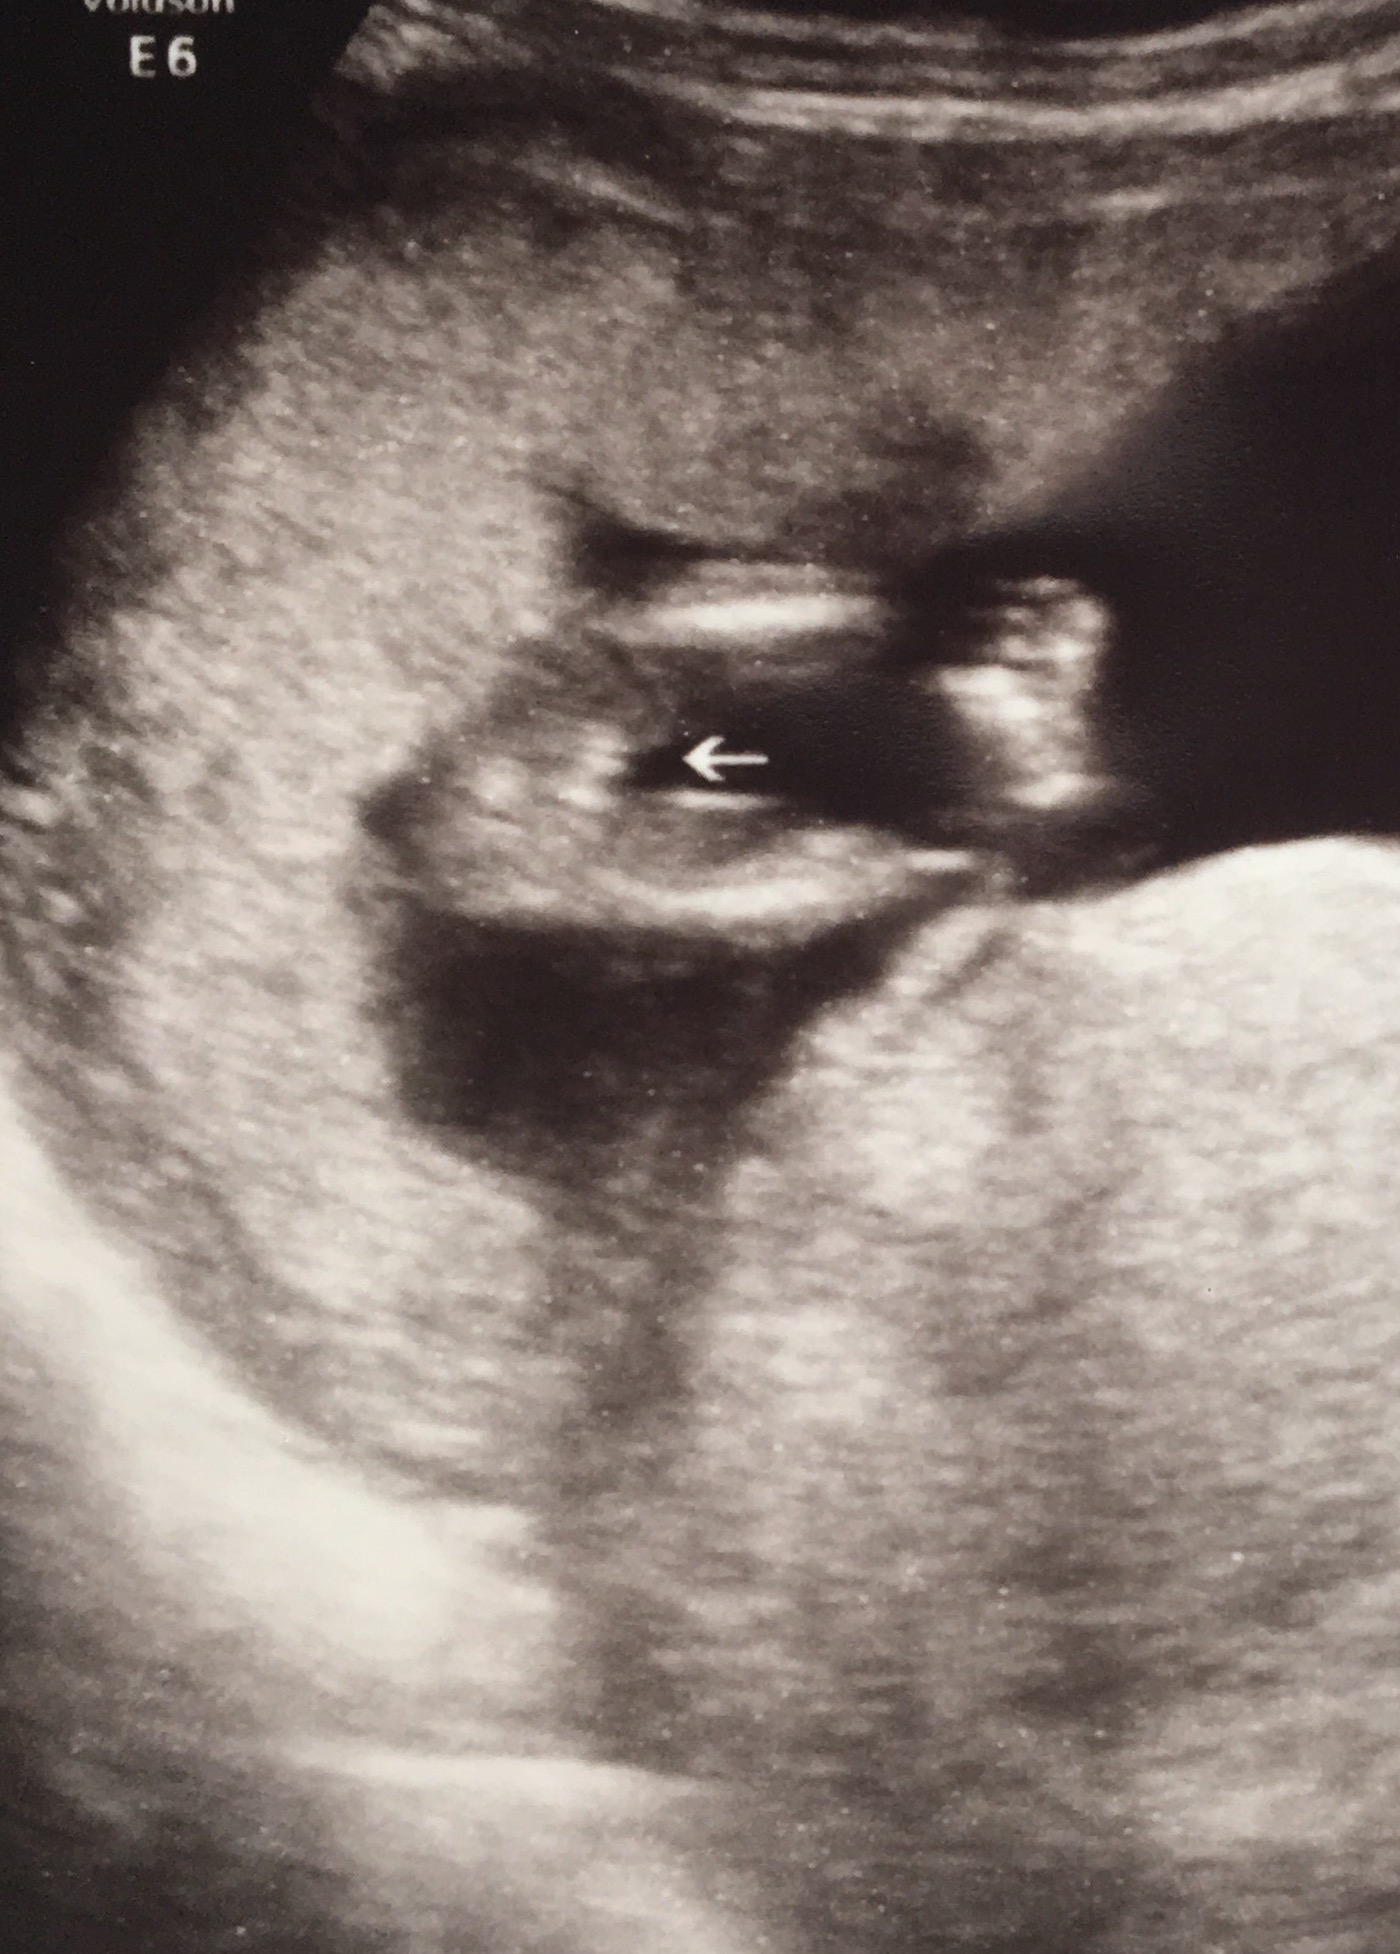

I had an elective gender scan at 15 weeks and the tech said that she was FOR SURE on the gender but

I just am not sure when I look at 2 of the 3 potty shots she gave me. I want it to be what she claims it is but I am just feeling a little unsure. Please give your input, it will be very very appreciated!! Attachment 36811Attachment 36812Attachment 36813